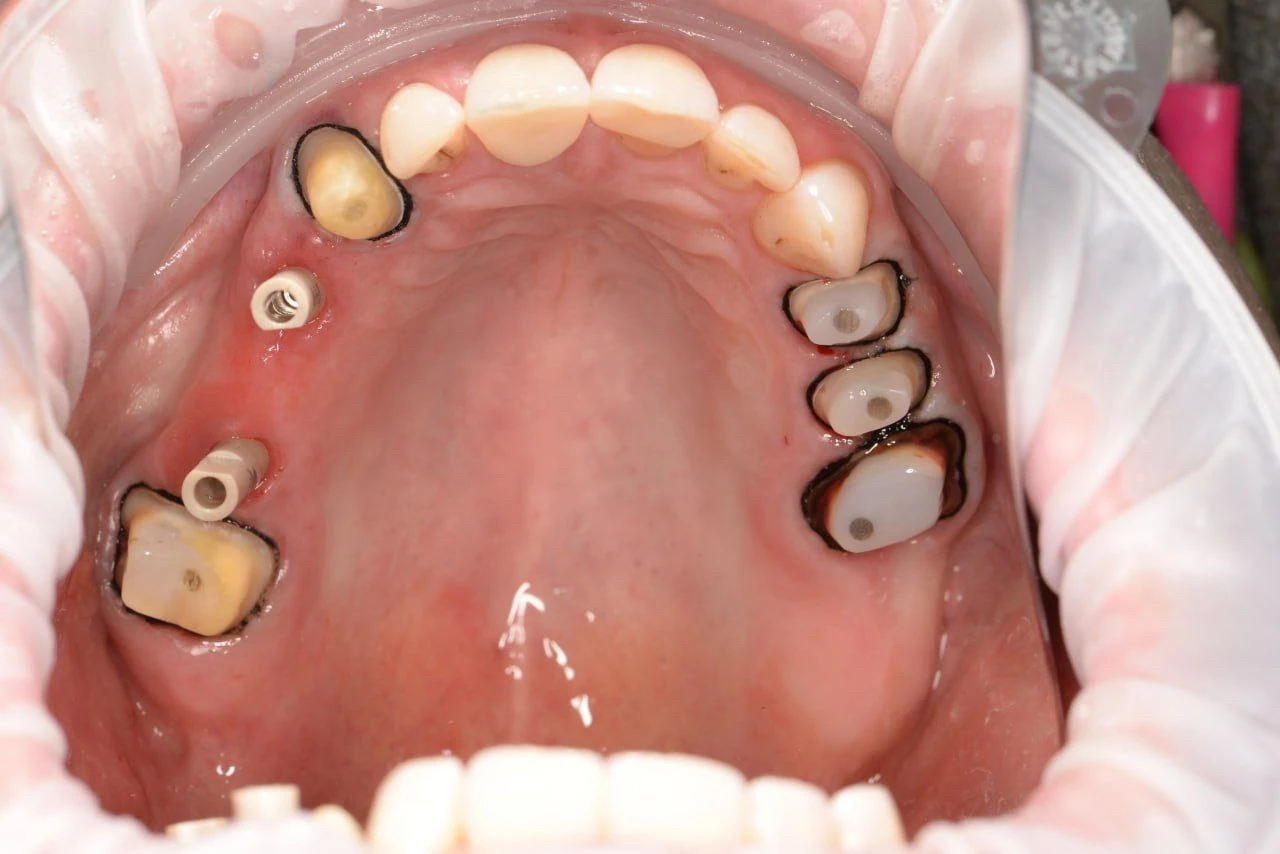

ЦК на 14.15.16.23.27 ЦК на премілах 24-26